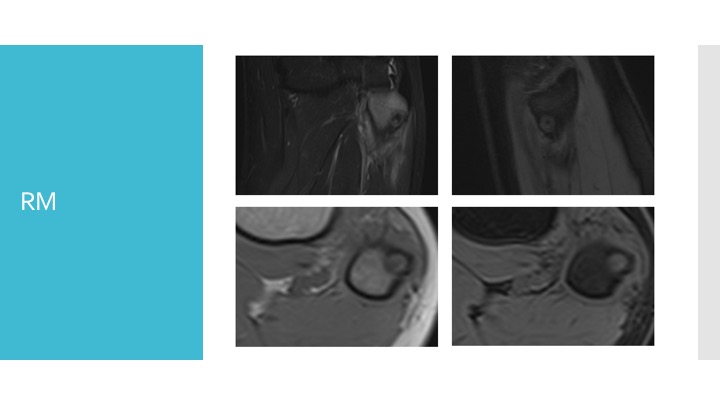

- Risonanza magnetica (RM): è un esame che utilizza campi magnetici per visualizzare sia le ossa che i tessuti circostanti.